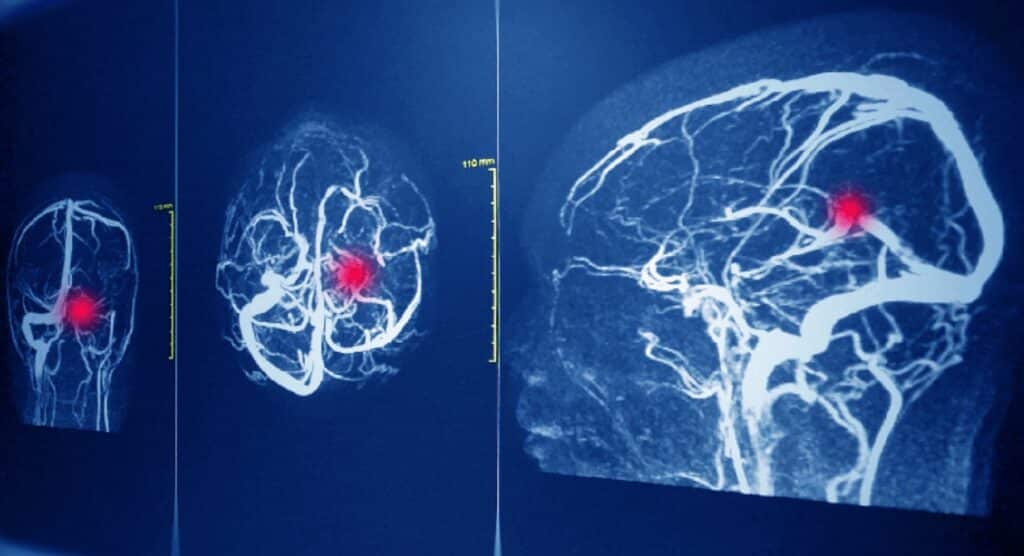

Un medico del San Camillo-Forlanini, Giuseppe Cicardo, sarà processato per omicidio colposo in ambito sanitario: il dottore è accusato di non aver riconosciuto un’aneurisma cerebrale ed aver rimandato a casa il paziente, diagnosticando solo una cervicale infiammata, sarà difeso dagli avvocati Claudio Ferrazza e Roberta Paglierella.

Il dott. Cicardo non avrebbe seguito così il protocollo che prevedeva una tac cerebrale di controllo.